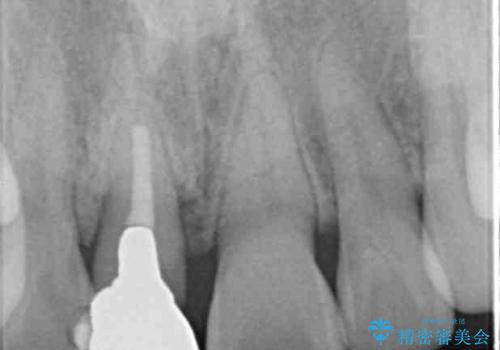

- 幼少期に前歯をぶつけて歯が折れ、神経の治療・クラウン治療を行った。グラつきと見た目の改善を希望して来院されました。

精密な仮歯をいれ、歯周組織を整えるとともにファイバーコア築盛、シェードテイキングを行い見た目に自然なジルコニアクラウンを製作していきます。